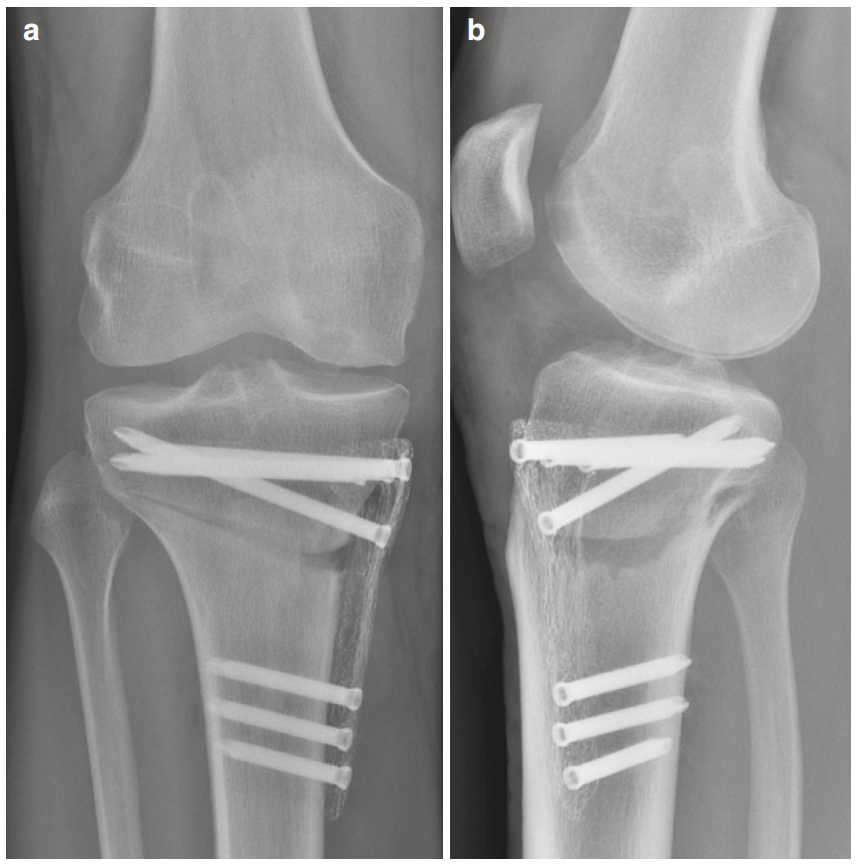

术后拍摄双平面X线片(图7与8)。

拍摄站立位全长正位X线片以评估新机械轴。

图7 (a, b)采用近端指向矢状面截骨并使用PeekPower HTO钢板(Arthrex)固定的内侧开放楔形胫骨高位截骨术(HTO)术后X线片。(a)正位视图,(b)侧位视图